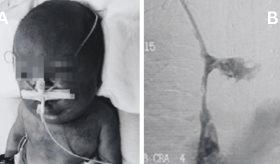

Estos pueden ocurrir "por un bloqueo del flujo sanguíneo en las arterias del cerebro, específicamente este se conoce como el ACV isquémico y si ocurre un rompimiento de esas arterias o hay un sangrado en el cerebro se conoce como un ACV hemorrágico".